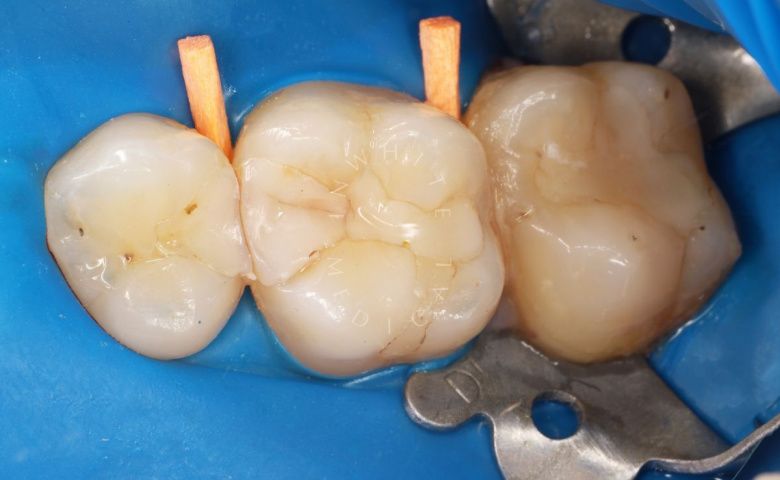

Художественная реставрация формы зубов

Стоматология Москва лучшие клиники. Художественная реставрация формы зубов - до процедуры

Стоматология Москва лучшие клиники. Художественная реставрация формы зубов - после процедуры